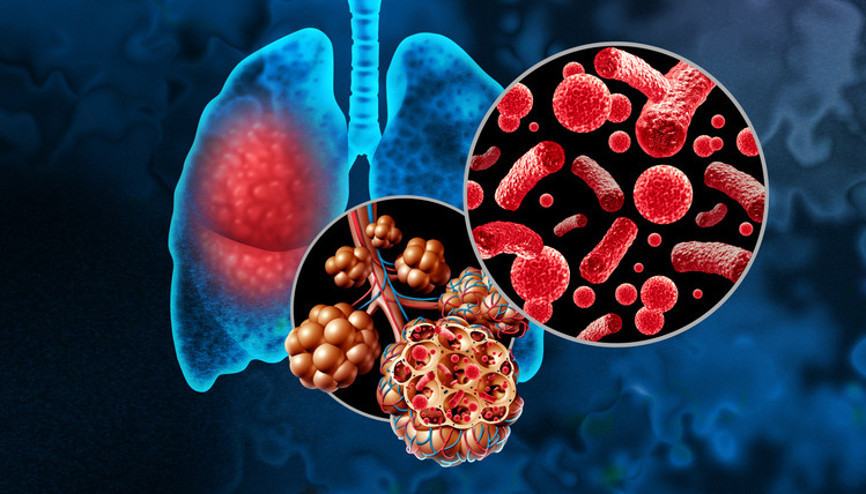

#SağlıkAkciğerlerin hava keseciklerinin en sık bakteriler, virüsler veya nadiren mantarlarla enfekte olarak iltihaplanması sonucunda zatürre oluşuyor. Dünyada her yıl yaklaşık 450 milyon kişiyi etkileyen bu hastalık, 4 milyona yakın insanın ölümüne neden oluyor. Grip veya COVID-19 gibi viral enfeksiyonlar da akciğerin savunma sistemini zayıflatarak bakteriyel zatürreye zemin hazırlıyor.

#SağlıkHalk arasında zatürre olarak bilinen pnömoni, akciğer dokusunun iltihaplanması sonucu oluşan bir hastalık. Dünyada ve ülkemizde hala en sık görülen enfeksiyonlardan biri olan zatürre aynı zamanda en önemli ölüm nedenleri arasında yer alıyor. Öyle ki ülkemizde her yıl yaklaşık 300 bin kişiye zatürre tanısı konuluyor. Sağlık Bakanlığı’nın 2023 yılı verilerine göre; hastaneye en çok yatış gerektiren bir enfeksiyon olan zatürre ölüm sebepleri arasında ilk 10'uncu sırada olmaya devam ediyor.

#ZatürreBursa’da, 5 yaşındaki Erdal Gazioğlu, gribal enfeksiyon sonrası gelişen zatürre nedeniyle yaşamını yitirdi. Bu acı olay, zatürrenin tehlikesini bir kez daha gündeme getirdi. Uzmanlar, üst solunum enfeksiyonlarının zatürre ile karıştırılmasının, hastalığın ciddiyetinin göz ardı edilmesine neden olduğunu vurguluyor. Prof. Dr. Muhammed Emin Akkoyunlu ise dünya genelinde her yıl yaklaşık 450 milyon kişinin zatürreye yakalandığını ve ülkemizde ise son bir aydır sayının arttığını belirtiyor. Peki zatürrede ölüme bile neden olan bu artışı nasıl yorumlamak gerekiyor? Belirtileri neler ve aşı ne kadar etkili?